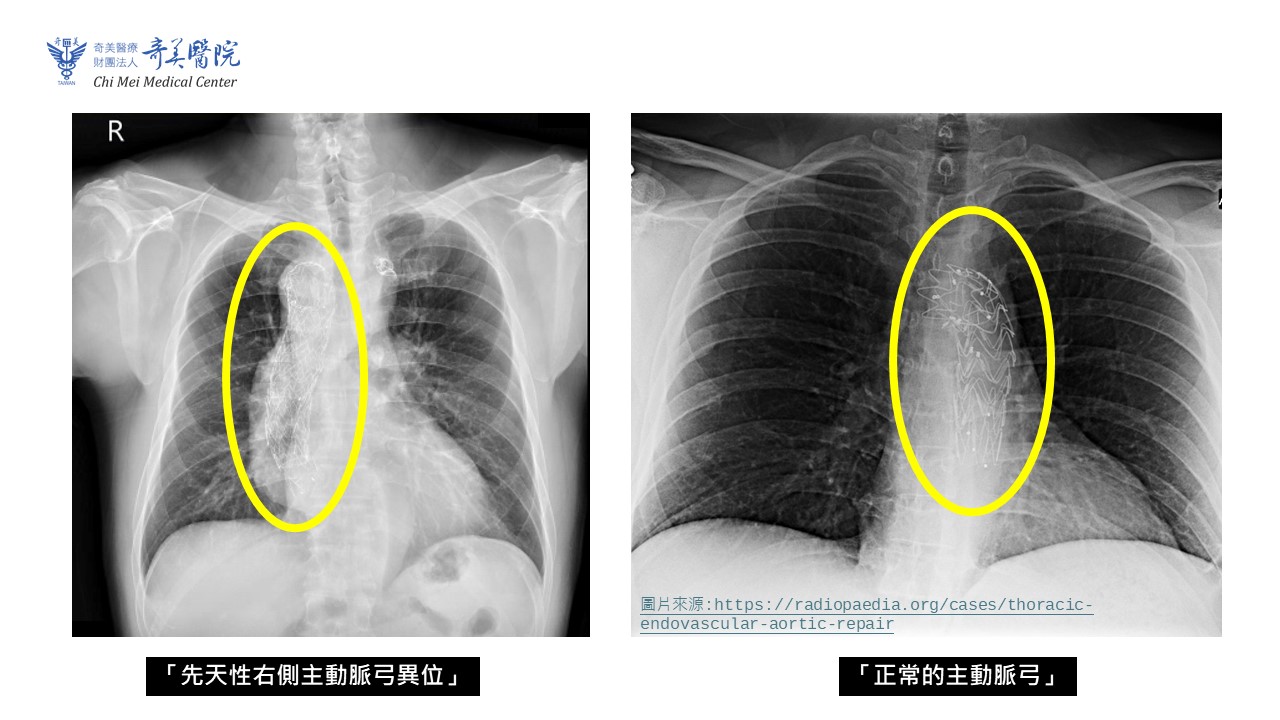

先天性右側主動脈弓異位與正常的主動脈弓比較圖(圖-奇美醫院提供)

吳南鈞進一步說明,純重度主動脈瓣逆流(AR)與常見的主動脈瓣狹窄其實不太一樣。主動脈瓣狹窄的病人因為瓣膜會變硬、鈣化,反而有利於人工瓣膜在置換時固定;但逆流型的瓣膜通常沒有鈣化、組織太軟,人工瓣膜放進去就像在泥沼裡,很難固定、容易移位,因此手術難度自然增加。若病人同時具有先天右側主動脈弓(主動脈走向與一般人不同,血管彎彎曲曲),又曾接受過胸主動脈內放置支架術(TEVAR),因血管路徑更為複雜,風險及手術難度也會更高。